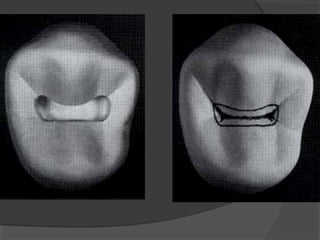

a) Class I Cavities:

Those cavities originating in anatomical pits and

fissures. They are found in the occlusal surface of

molars and premolars.